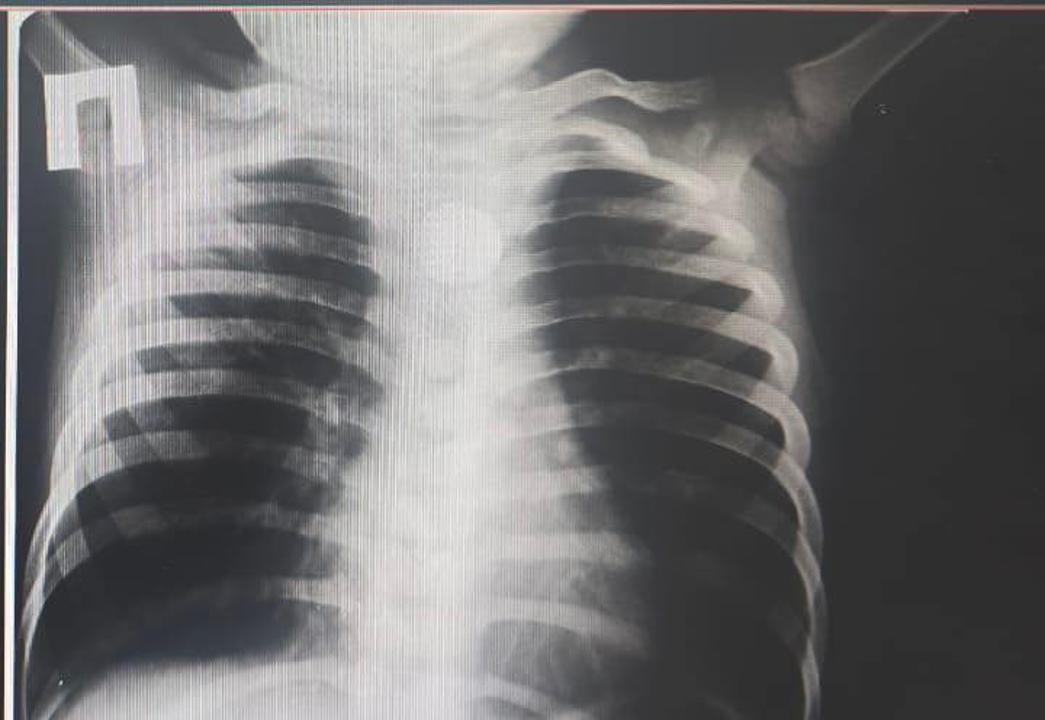

"По словам матери, после еды мальчик неожиданно начал сильно кашлять, его стошнило, появилось обильное слюноотделение. Родители немедленно обратились за медицинской помощью. При рентгенологическом обследовании в районной больнице врачи обнаружили, что в пищеводе ребенка застрял круглый металлический предмет — батарейка", - рассказали подробности инцидента в акимате региона.

Медики приняли решение о срочной транспортировке в Туркестанскую областную детскую больницу. Скорая помощь оперативно доставила пациента, где его уже ожидала бригада хирургов и эндоскопистов. После осмотра и дополнительных исследований рентген подтвердил: инородное тело находилось в верхней трети пищевода, что представляло серьезную угрозу жизни.